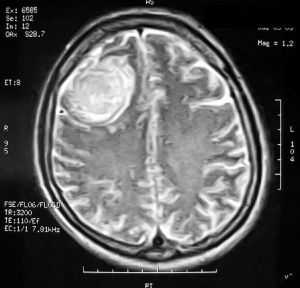

Пациентка В., 25 лет. В возрасте 9 лет перенесла острый лимфобластный лейкоз, по поводу чего проводилась лучевая терапия.

За 2 месяца до поступления в стационар появилась боль в левой височной области, левом глазном яблоке, слезотечение. Консультирована офтальмологом — выявлено высотные левого глазного яблока на 6 мм, по сравнению с правом глазным яблоком, а также признаки внутричерепной гипертензии в виде застойных дисков зрительных нервов. При МРТ выявлена больших размером внемозговая опухоль средней черепной ямки с гиперостозом и распространением в глазницу слева.

Выполнена операция — удаление менингиомы крыльев клиновидной кости с резекцией гиперостоза и использоваием интраоперационной метаболической навигации (ультрафиолетовая флюоресцентная микроскопия)